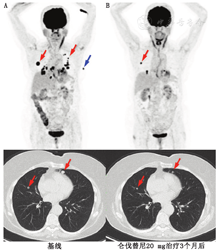

最近发表了使用仑伐替尼治疗晚期DTC的Ⅲ期临床试验数据[36]。使用RECIST 1.1评价,治疗组的总有效率为65%,安慰剂组为2%,2组中位无进展生存期分别为18和4个月。此外,在这项试验中,由于患者病情进展后才改用开放标签药物,也未能观察到2组总生率差异有统计学意义。然而,在亚组分析中,与安慰剂组相比,治疗组中65岁或65岁以上患者的总生存率有所改善[35]。1例仑伐替尼的治疗效果示例如图1。由于毒性的原因,对82%的患者必须改变给药方式。2015年2月,该药物在美国被批准用于治疗局部复发或转移性的进展性RAIR DTC患者。目前,仑伐替尼治疗RAIR DTC患者的Ⅱ期临床试验正在进行,以评估每天18 mg的口服起始剂量能否在改善毒性作用的同时获得与常规24 mg起始剂量相当的疗效。